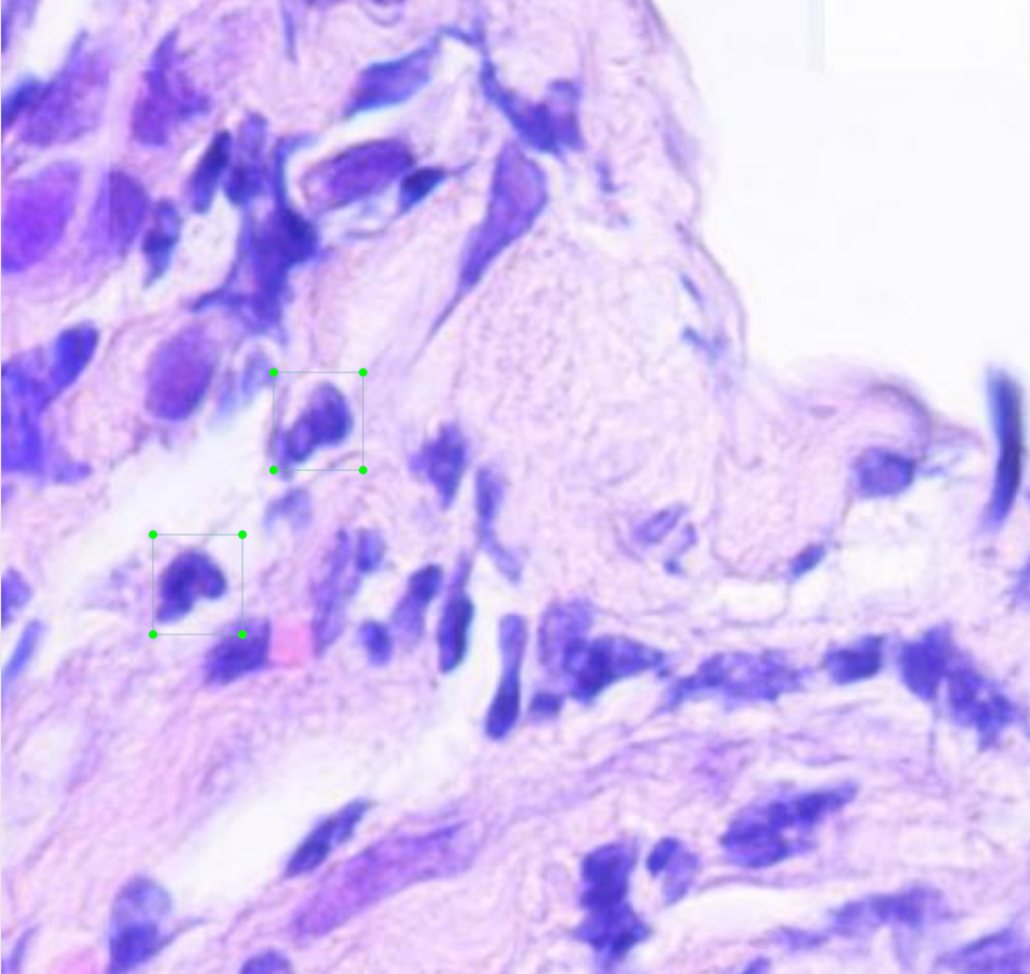

In Mateo's case, an individually labeled example appeared like the following:

After an image is tiled, it is run through the model to count neutrophils, and the team then reconstructs the individual tiles to create a full image output.

A prediction for one of these individual tiles appears like the following: